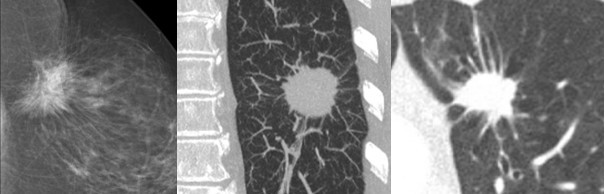

十、结节是中性词,有良性恶性之分;长相规则圆溜、边缘光滑齐整的结节通常是良性的,张牙舞爪、浸润性生长的结节则可能是恶性的

最后一个问题,也是很多患者在问的。现在做体检的人越来越多了,有患者就会拿着体检报告来找我,说肺上长了一个结节,坏了,我得癌了,包括一些朋友也恐惧自己报告上的结节是不是指的肿瘤,这其实存在一个误区。

影像科报告的“结节”是一个形态描述,是个中性词;就相当于我们提到“人”,只是一个客观描述,并不代表是好人还是坏人。结节也是一样,有良性结节和恶性结节之分。

图片(影像结果示例)

左边这张图,是一个乳腺的结节,中间和右边的图是肺结节。大家看,圆溜溜的,像玻璃球一样的,边缘也很光滑,这是良性的表现。小的甚至不需要任何处理。

大家再看这组病例,左边还是乳腺结节,中间和右边的是肺结节。这些结节的边缘都很毛糙,像有很多小爪伸出来,专业词汇叫“毛刺”或“浸润生长”,这是恶性的一个比较典型的特征,恶性肿瘤往往是浸润生长的。

所以这也是为什么恶性肿瘤不好治的重要原因之一,因为它浸润生长的行为,常会侵犯到周围的脏器,或侵入血管导致远处转移、全身播散,导致很难被根除。癌症“Cancer”这个词来自于拉丁语“螃蟹”的意思,很形象。你看它长得张牙舞爪,像螃蟹一样的,可能就是恶性的。